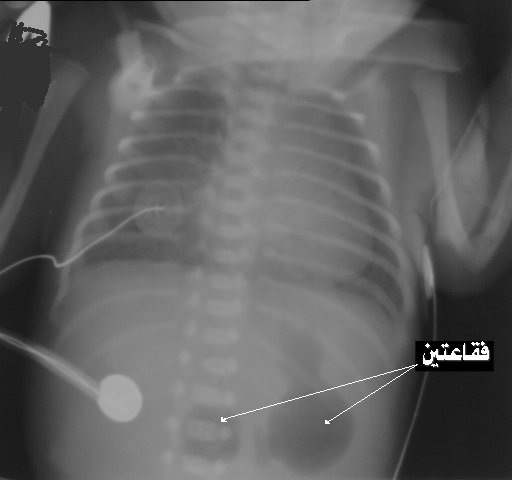

Congenital Duodenal Obstruction And Double-Bubble Sign

Duodenum (arrowhead) — which is pathognomonic of congenital duodenal obstruction. Laparoscopy showed duodenal atresia type 1, which was repaired with a diamond-shaped duodenal anastomosis. Oral feedings were initiated successfully on the seventh ... Content Retrieval